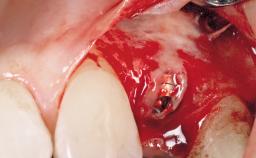

Immediate Flapless Placement of an Implant in a Maxillary Left Central Incisor Site

A 42-year-old female patient was referred to our clinic at the School of Dentistry of the University of São Paulo in November 2004, presenting a deficient restoration in the upper left central incisor. The clinical examination revealed no gingival retraction or any signs of gingival inflammation and, therefore, previous periodontal treatment was not considered. The patient presented a high lip line at full smile and a thin tissue biotype. This combination characterized a high-risk situation from an anatomic point of view, which required careful preoperative planning and cautious surgical execution.

| Placement Protocol | Immediate implant placement |

| Socket Morphology | Single-root socket |

| Socket Integrity | Sufficient, with intact bone walls |

| Bone Volume | Sufficient, with intact walls |